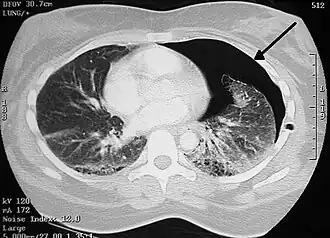

![]() Правосторонний спонтанный пневмоторакс (слева на изображении). Стрелкой указан край спавшегося лёгкого. | |